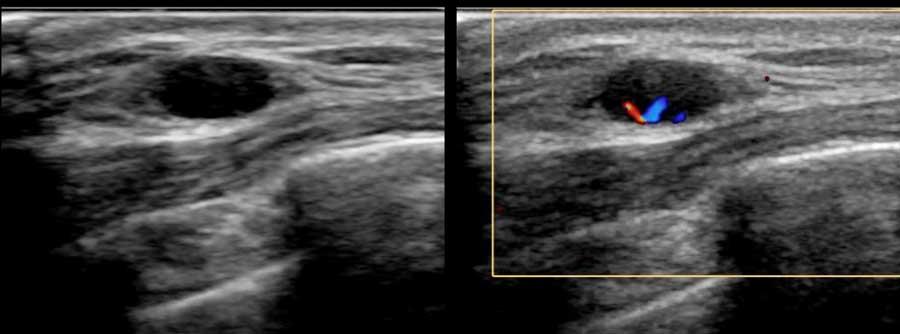

Khi thấy có mạch máu trên siêu âm Doppler màu thì đó là khối u trong nang, có thể lành tính hoặc ác tính.

Đây là một khối u có thành phần dạng nang chứ không phải là một nang đơn thuần.

Đây là một trường hợp ung thư vú khác có thành phần dạng nang.

Lưu ý thành phần đặc lớn với dòng chảy trên hình ảnh Doppler.